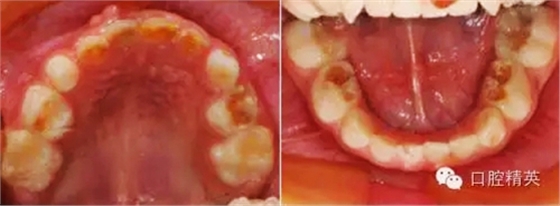

臨床檢查:頜面部及頸部未見明顯異常。口腔衛(wèi)生狀況尚可, 52,61,62,63,73唇舌面齲,54,64,74,84牙合面齲壞,腐質(zhì)中等,叩(-),松(-),牙齦未見明顯異常;75牙合面深齲壞,大量軟腐,叩(-),松(-),牙齦未見明顯異常,腐質(zhì)未去凈見露髓孔;51大面積齲壞,大量腐質(zhì),叩(+),松(Ⅰ),唇側(cè)牙齦可見5mm×6mm的包,軟;余牙未見異常。

診斷:S-ECC